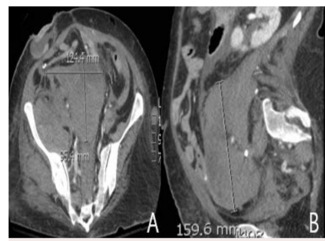

A case of lumbar and internal iliac artery pseudoaneurysms following cecal perforation.